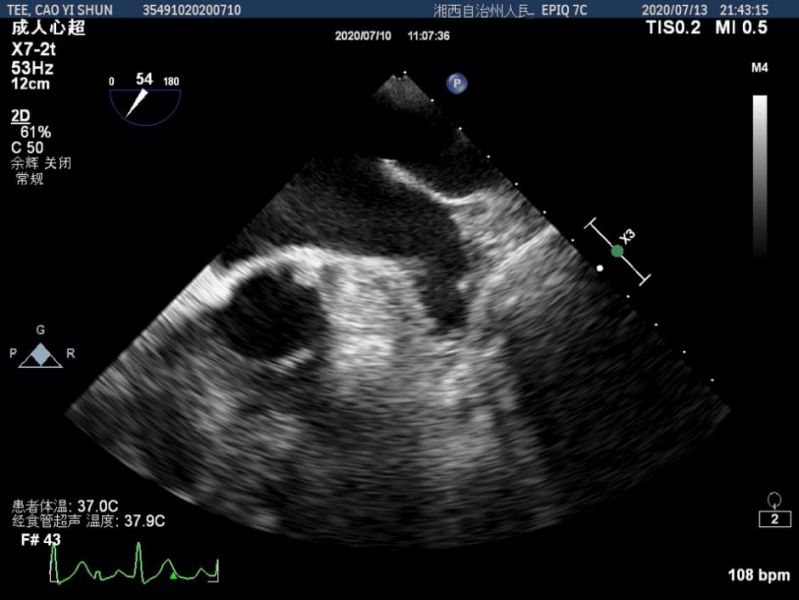

经食道超声心动图图像显示。